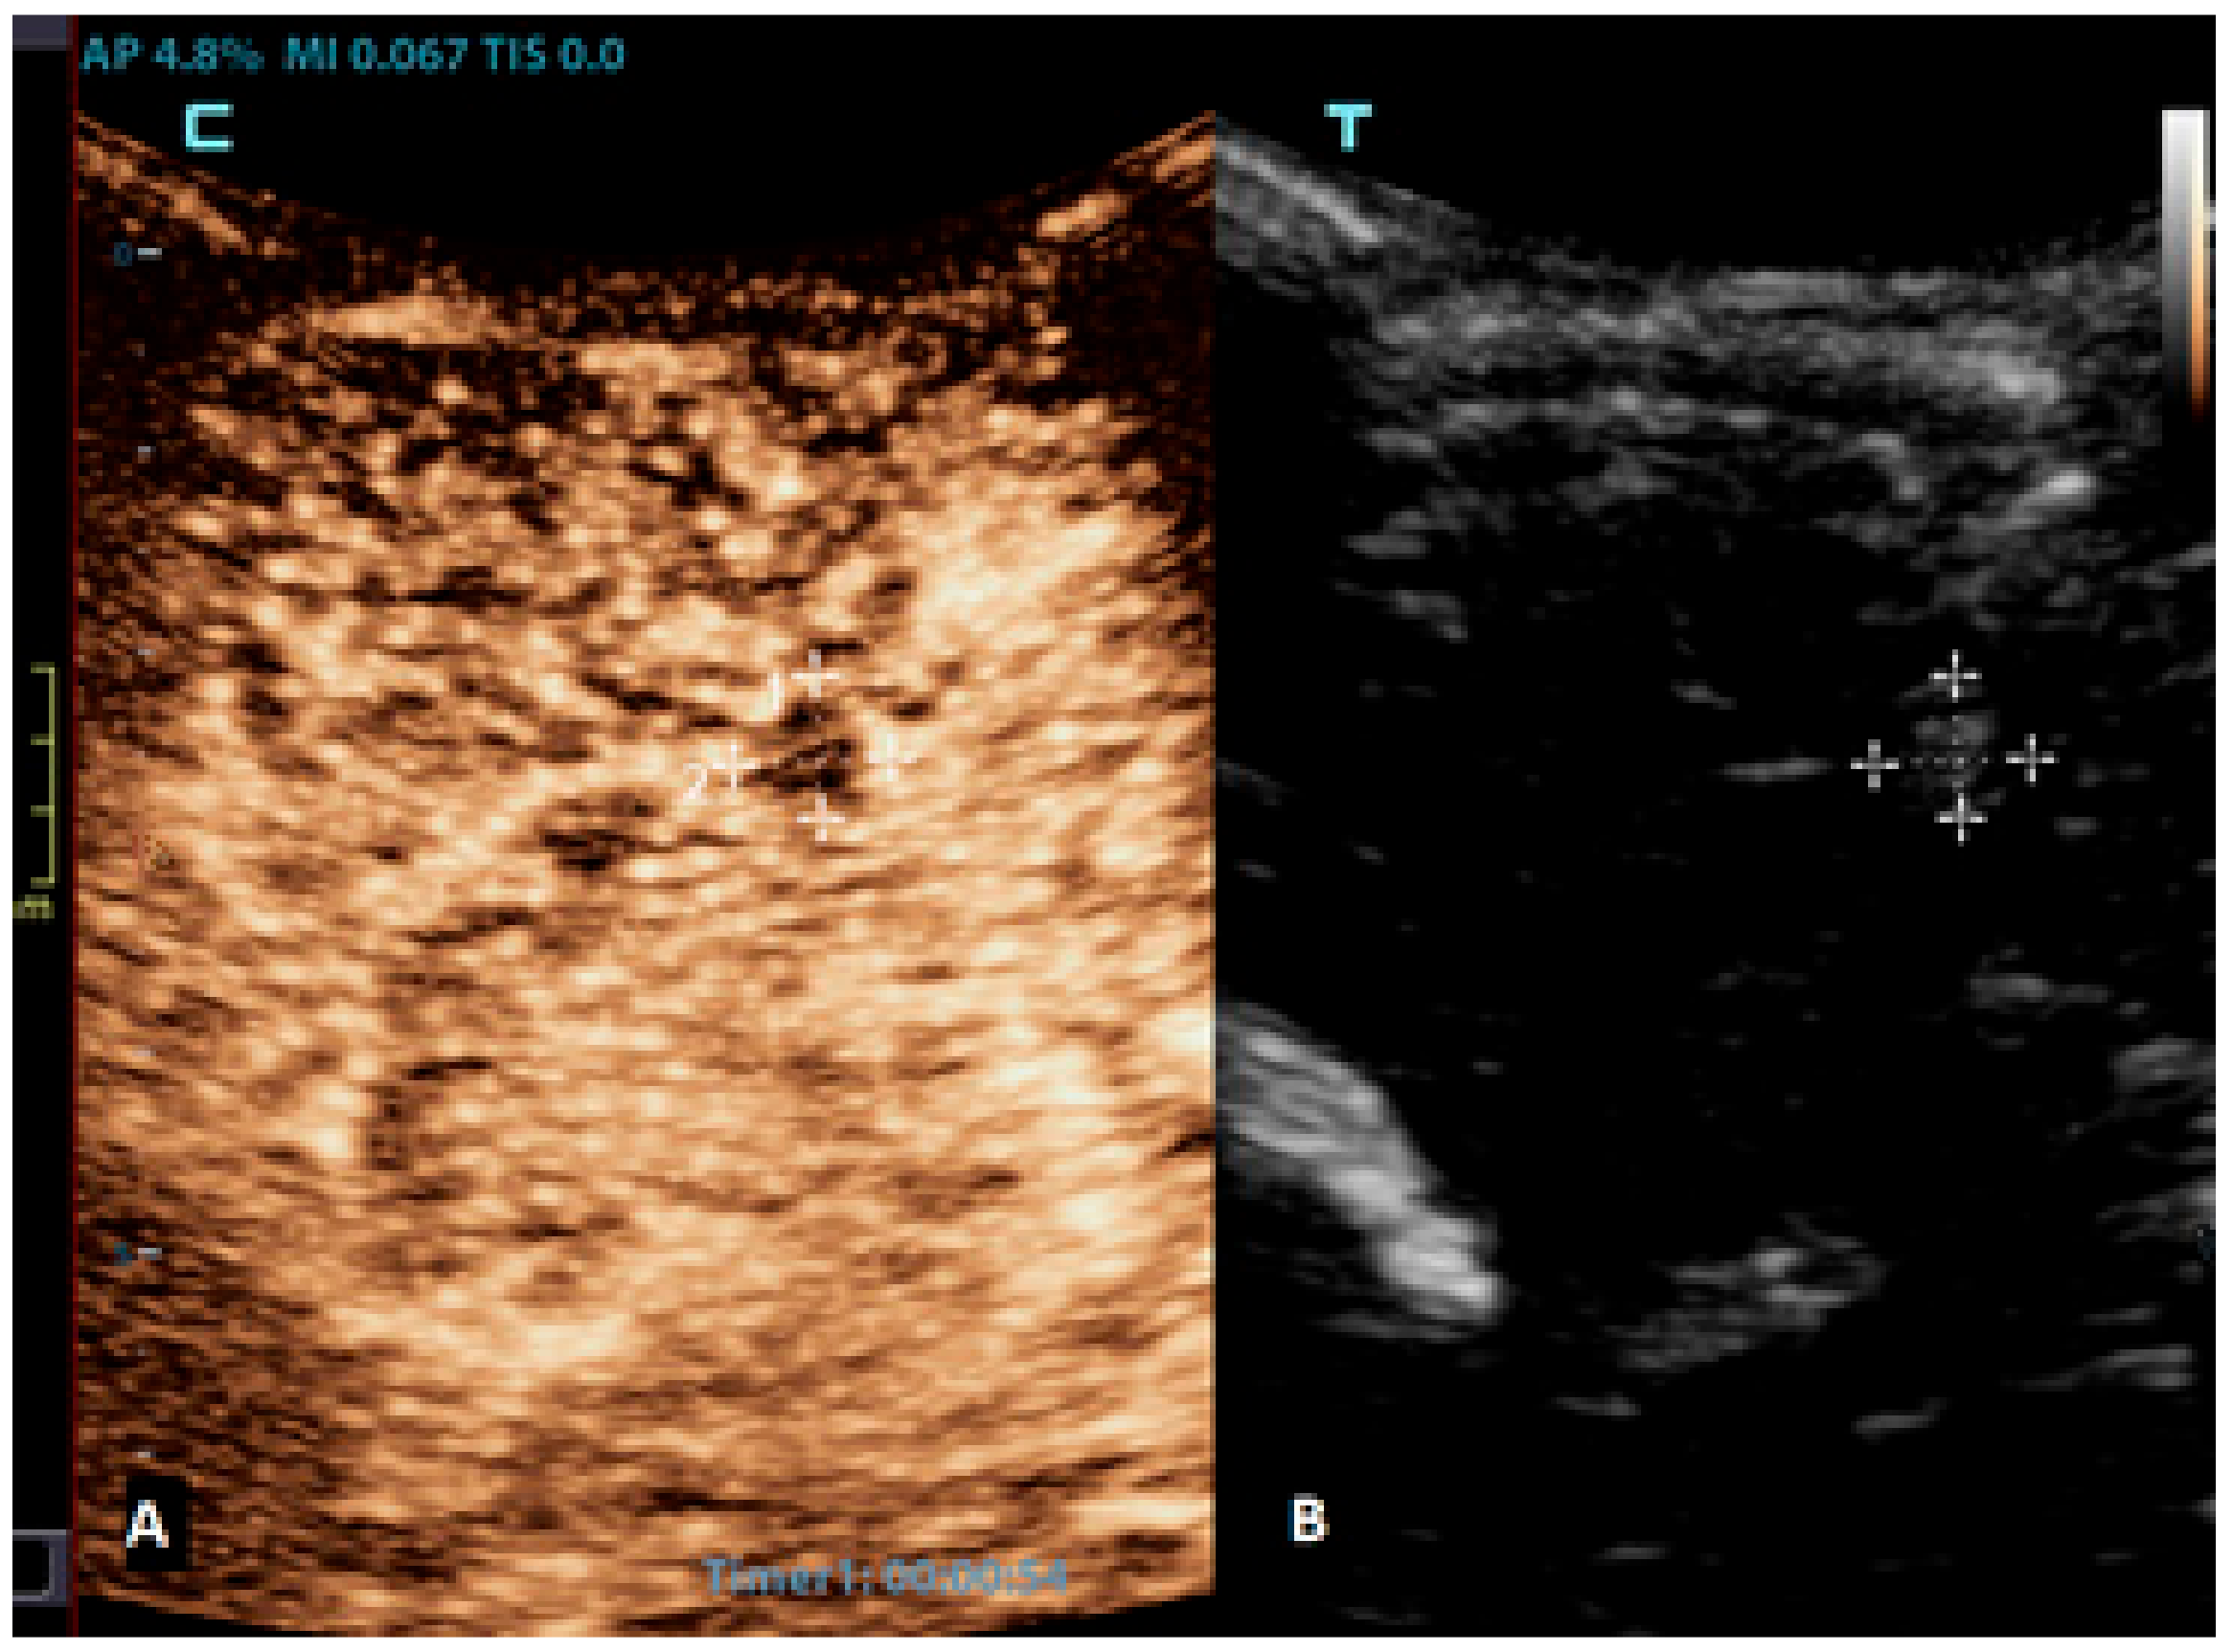

Figure 4.

A 6-month-old premature boy with an accidentally detected small lesion in the 4th ventricle. (A) The transverse reference grayscale ultrasound image through the left mastoid fontanelle. (B) The transverse CEUS image of the 4th ventricle demonstrates avid arterial and venous enhancement of the lesion (arrows). Findings were suggestive of choroid plexus papilloma; subsequent brain MRI scans confirmed benign aetiology of the lesion.